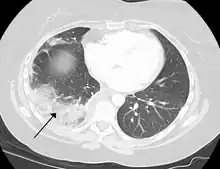

- Lung: Pulmonary infarction or lung infarction